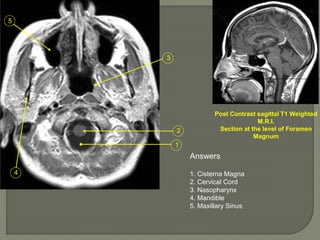

Post Contrast sagittal T1 Weighted

M.R.I.

Section at the level of Foramen

Magnum

Answers

1. Cisterna Magna

2. Cervical Cord

3. Nasopharynx

4. Mandible

5. Maxillary Sinus